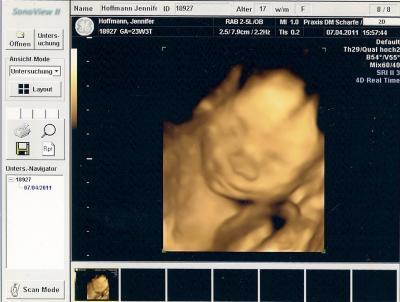

war ja heute wieder beim frauenarzt un alles ist in ornung die kleine hat ordentlich zugelegt. Sie ist ca. 29,4 cm groß und wiegt 560 g.

Vor zwei wochen war ich ja schonmal da weil ich auf den bauch gefallen bin un da war sie ca. 21 cm groß und 321g schwer also hat sich in zwei wochen viel getan würde ich sagen

BPD: 5.9 cm

KU: 21.3 cm

ATD: 5.3 cm

AU: 17.2 cm

FL: 4.2 cm

Achja die kleine liegt auch schon mit dem köpchen nach unten.